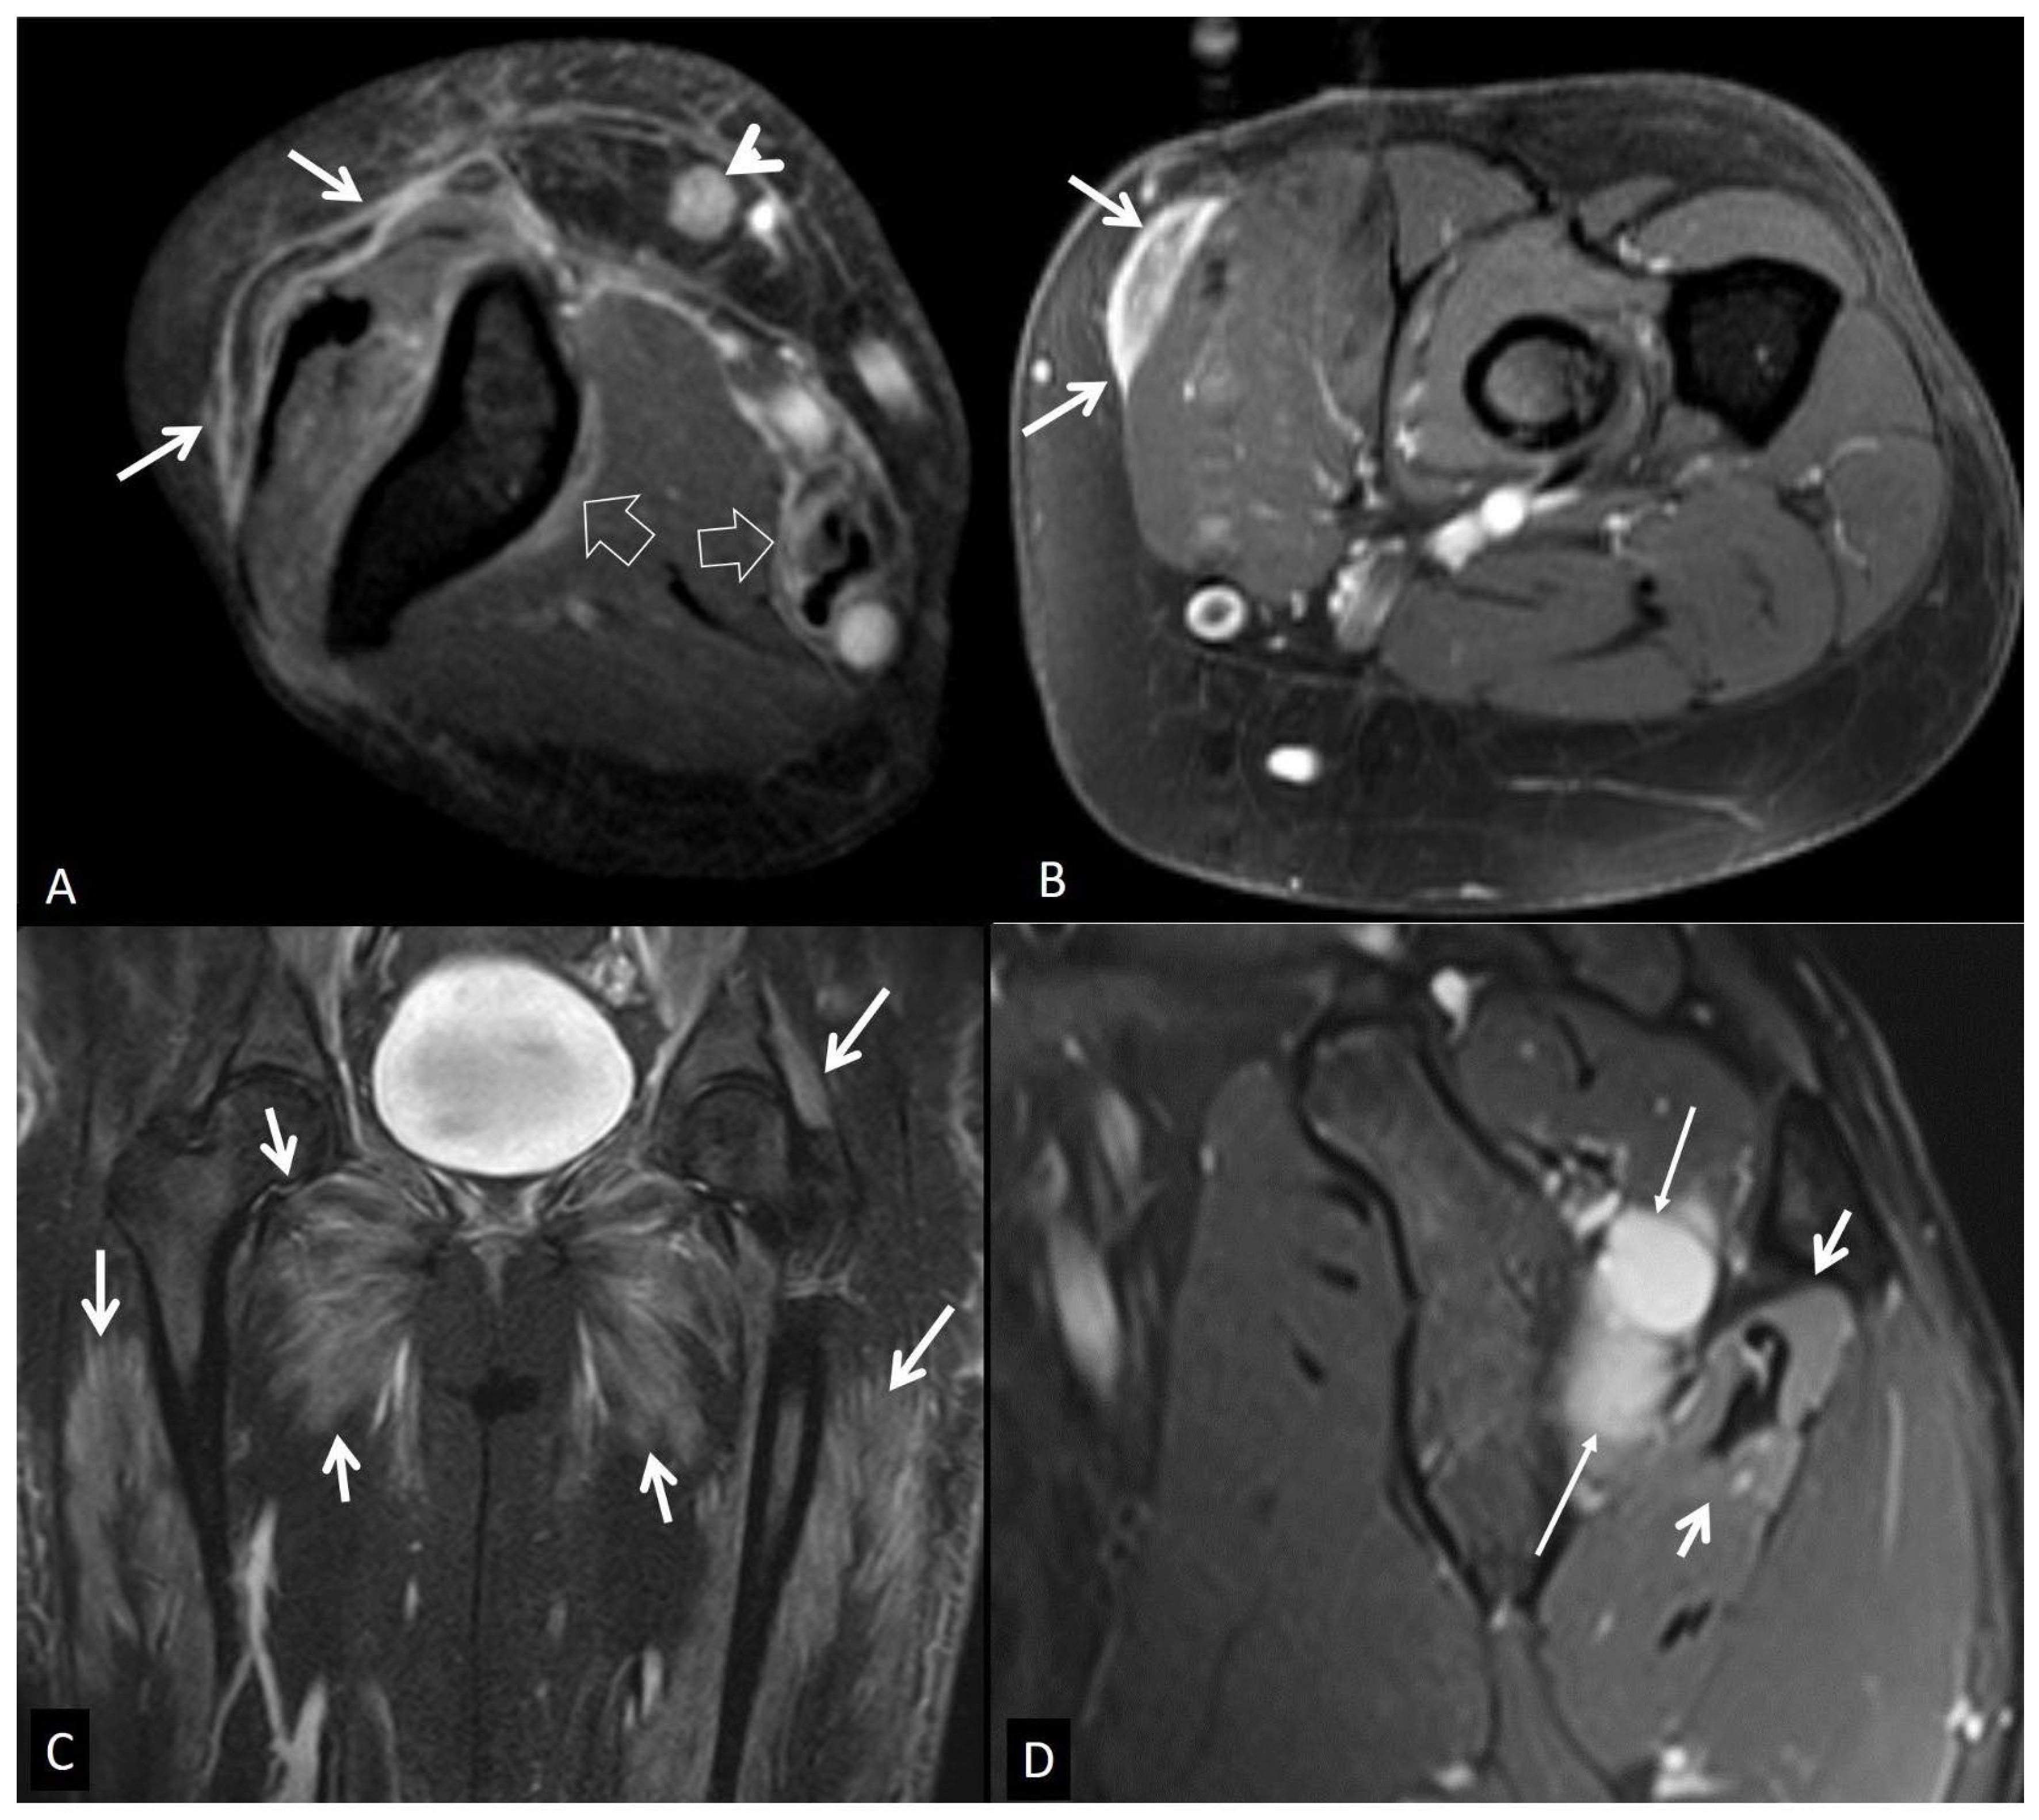

3. b.iii Crystal-Induced Arthropathies

3. b.iv. Rapidly Destructive Osteoarthritis of the Hip

3. b.v. Neoplasms

4. Muscles and Soft Tissues